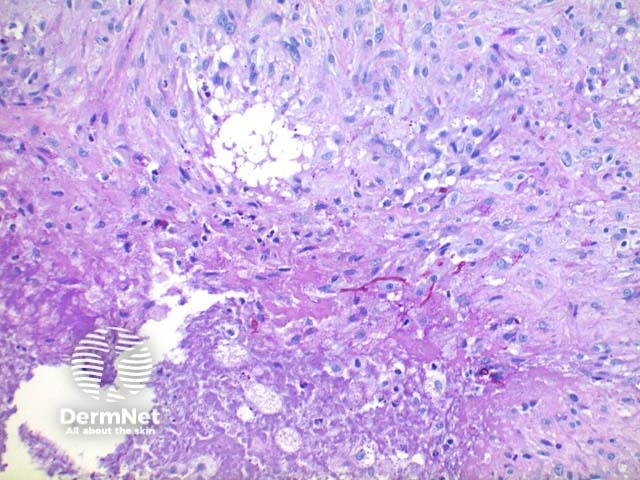

Scanning power view of phaeohyphomycosis shows a deeply extending granulomatous pattern (Figure 1) which may show areas of necrosis (Figure 2). Centrally an abscess or cystic nodule may form. Frequently a foreign body such as a wood splinter can be seen. The epidermis commonly shows pseudoepitheliomatous hyperplasia. The inflammatory infiltrate is comprised of histiocytes with multinucleated giant cells, and numerous neutrophils (Figures 3,4 and 5). At high power branching septate pigmented fungal hyphae can be seen (Figure 6).

Figure 4